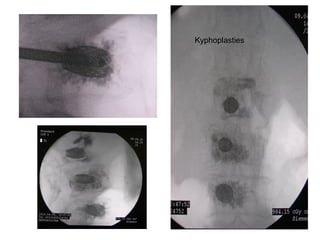

Kyphoplasty

kidney’s metastasis

Kyphoplasties

• Osteoporosis

– Vertebroplasty

– Kyphoplasty